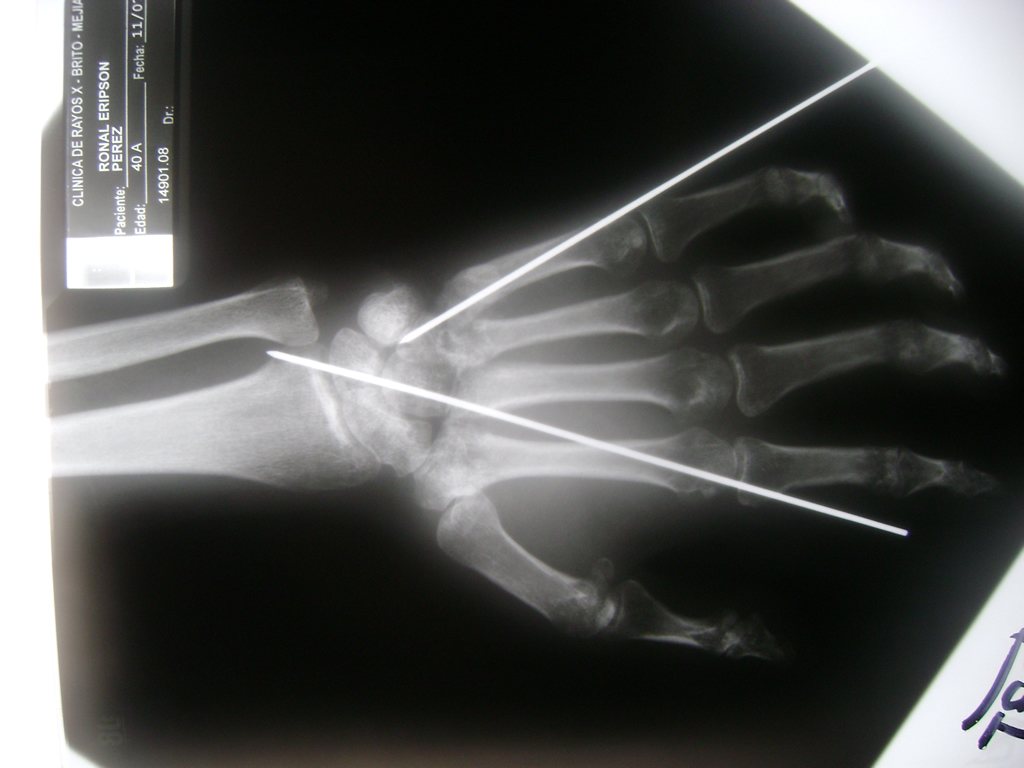

Cirugías de Muñecas

Los procedimientos más comunes en cirugía de la mano son aquellos destinados a reparar traumatismos, incluyendo lesiones de tendones, nervios, vasos sanguíneos, y articulaciones; huesos fracturados; y quemaduras, cortes, y otros daños de la piel.